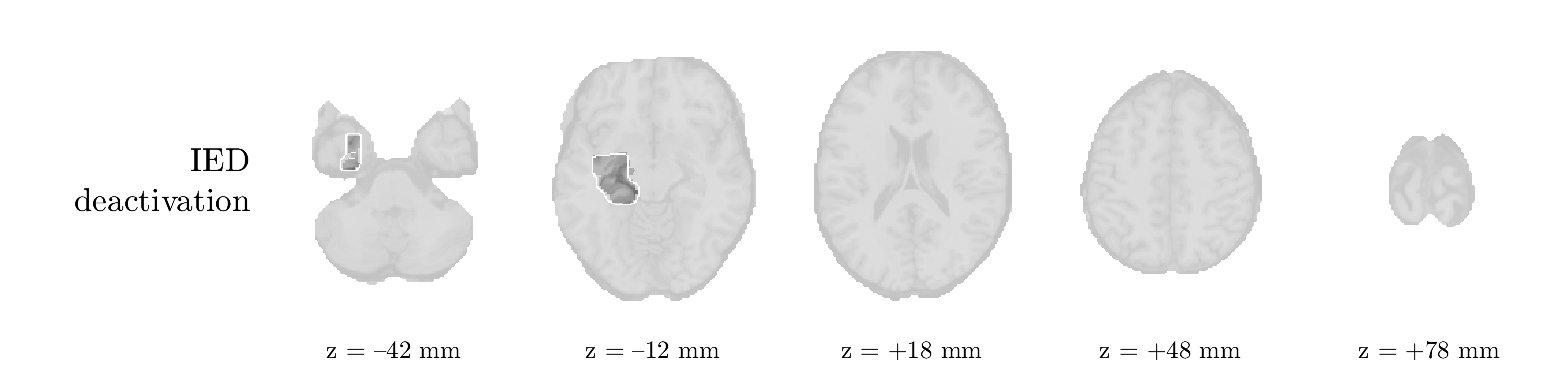

Patient 9

We analyze the solution with sources, and show the results in Figure 15 and 16. In this patient, there is only a moderate correlation of a component with the MWF reference time course. This component’s topography (left occipital) agrees with the clinical description, however. The HRF extremity (and not the entropy) is high in a small part of the IOZ. Both the significant IED activation and deactivation allow correct localization as well. The second source seemingly captured high-frequency oscillatory activity in the sensorimotor network, similar to the previous patient.